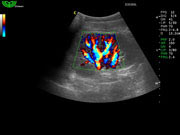

Система поддерживает СFM-режим, PW-режим, CW-режим, режим направленного энергетического потока, режим Color-M, панорамный режим, ECG, DICOM 3.0 и универсальные пакеты программ для кардиологии, сосудистого исследования и акушерства.

Режимы изображения: B, 2B, B/M, B/BC, CFM, PW, HPRF, PD, направленный PD, CW, режим Color M.

Многократное составное отображение (MCI)

Как в бестеневой лампе, ультразвуковая волна передается под разными углами для предоставления врачу большего количества информации и получения более качественных изображений.

В этом специальном режиме сканирования B датчик передает звуковые волны не только перпендикулярно, а также и в других плоскостях, вращая направление распространения волн. Затем эти плоскости перекрываются и формируют конечное изображение. Это улучшает пространственное и контрастное разрешение и уменьшает отражения на границе.

- Увеличивает линейную плотность, улучшает качество изображения.

- Улучшает контрастное разрешение; позволяет более четко различать слои тканей и края сосудов.

- Уменьшает поперечный эффект на границах тканей, что делает органы более различимыми.

- Уменьшает тени, создаваемые звуковой волной.